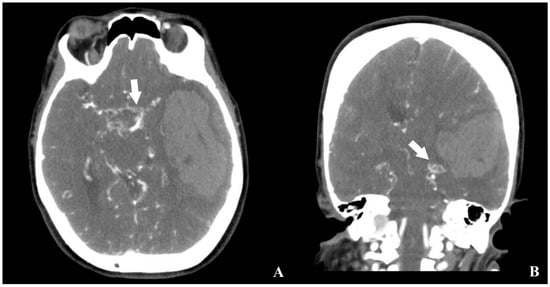

An emergent brain CT demonstrated a 48 mm × 75 mm intraparenchymal hematoma in the left temporal and insular lobes, with a 16 mm midline shift to the right, as well as multiple burr hole defects (Figure 1).

Figure 1. Initial brain CT obtained at the patient’s presentation to the emergency department ((A) axial, (B) sagittal, (C) coronal view). The scan demonstrates a large intraparenchymal hematoma in the left temporal and insular lobes, accompanied by a significant midline shift to the right and mass effect with compression of the adjacent ventricular structures. Multiple burr hole defects from the previous revascularization procedure are also visible.